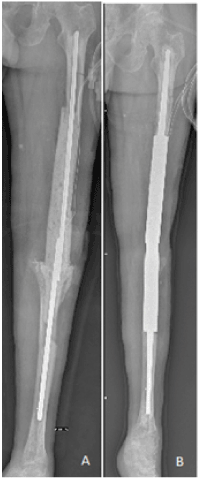

Figure 3. Antibiotics-added cement spacer in arthrodesis and silver-coated prosthesis in arthrodesis after removal of the spacer